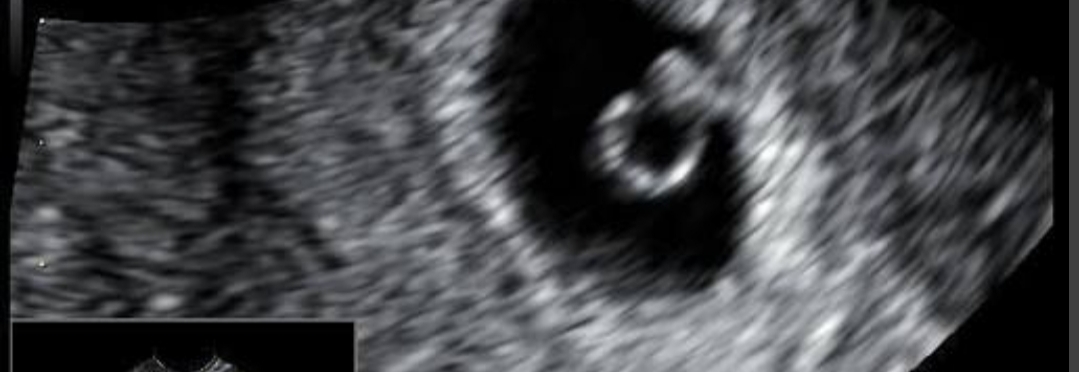

Udało mi się szybko dostać do ginekologa. Uspokoiła mnie trochę że to bardziej wydzielina niz krew. Zrobiła USG i wychodzi 5+0 czyli tydzień młodsza nic z OM. Póki co mamy pęcherzyk, mam nadzieję że lada moment pojawi się zarodek z serduszkiem 🥺🍀 no i mam brać duphaston, kolejna wizyta 24.03 🙏

https://zapodaj.net/plik-X0iNvDtrOD

Przedstawiam Wam moje jajeczko ♥️Wiadomość wyedytowana przez autora: 16 marca, 19:33